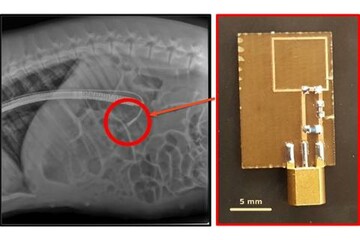

Draper, MIT and Brigham and Women’s Hospital developed an ingestible biosensor for the digestive tract that addresses a common problem with implantable devices: How do you power them? Image credit: MIT, Draper